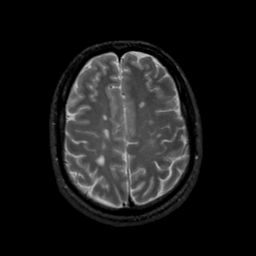

MR Study #22, December 1, 1991 -- Slice #37

[Home][Help][Clinical][Tour 1][Tour 2] Slice 37